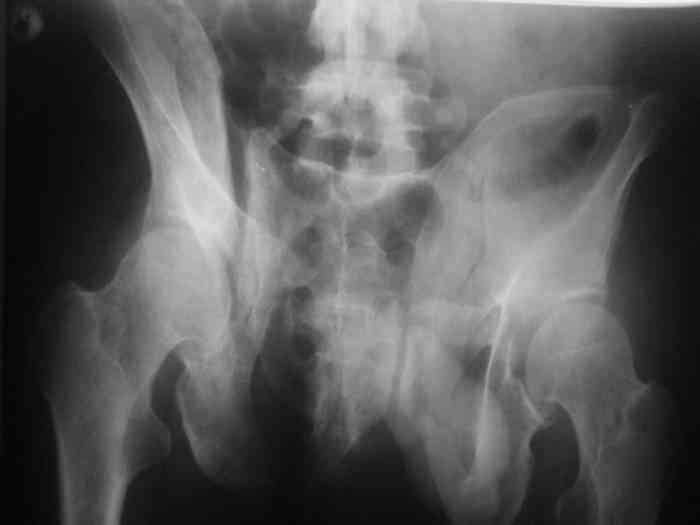

Остается только вариант закрытого аппаратного лечения. В аттаче положение отломков на вытяжении в прямой (АР) проекции. Для сравнения снимок до и во время вытяжения.

> Остается только вариант закрытого аппаратного лечения.. В аттаче

> положение отломков на вытяжении в прямой (АР) проекции. Для сравнения

> снимок до и во время вытяжения.

Только аппаратными методами в этом случае проблему не решить (фактически вы имеете дело с болтающимися псевдоартрозами), потребуется открытое вмешательство.

разрыв КП с перелом задней ости (стержни в нее не вкрутишь), и срок после травмы (аппарат болен быть более мощным, крутить медленно и долго).

С другой стороны переломы, если они срастутся, полностью восстановят стабильность (с чистыми разрывами так не получится). Остается добиться пусть даже не идеального контакта между отломками, закрыто или открыто вопрос техники.